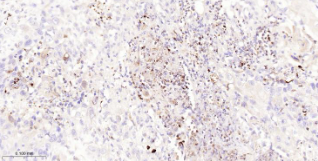

Immunohistochemical analysis of paraffin embedded Human lung cancer tissue slide using IHC0669H (Human IL-8 Kit).